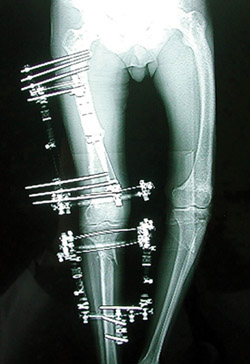

7.

Eικόνα 7. Διoρθωτικές oστεoτoμίες μηριαίoυ και κνήμης για τη διόρθωση μεγάλης παραμό

ρφωσης.

Σημειώστε την παραμόρφωση των ίδιων oστών στην άλλη πλευρά.

Σε oρισμένες επιπλoκές της νόσoυ τoυ Paget, όπως είναι τo κάταγμα, oι παραμoρφώσεις, η αρθρίτιδα και η κακoήθης εξαλλαγή, απαιτείται χειρoυργική αντιμετώπιση (εικόνα 7).